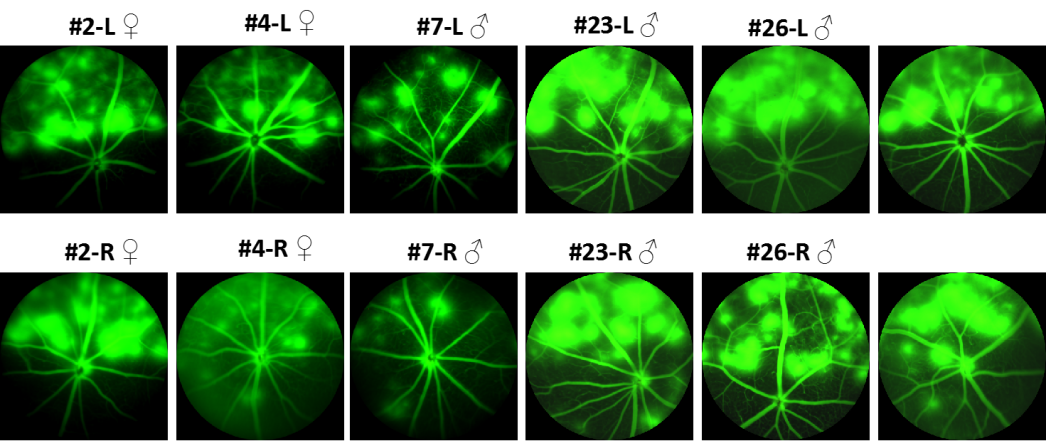

FFA(眼底荧光血管造影)结果显示:F1小鼠能复现F0表型。

hVEGF小鼠(F1)眼底荧光血管造影结果